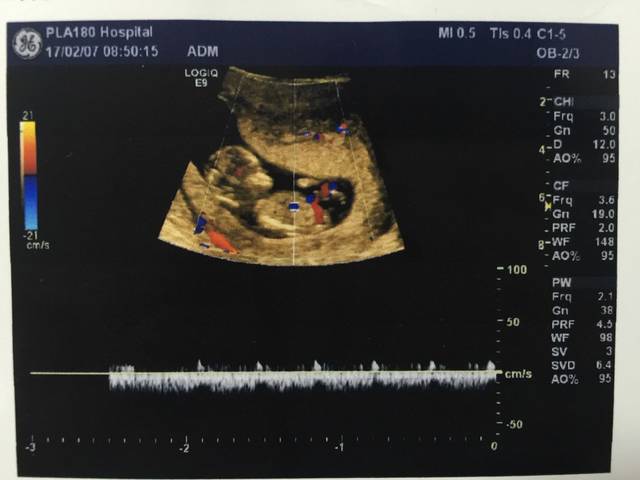

nt增厚,2.91。需要做绒毛穿刺么?

简介:NT是什么?NT(nuchal translucency),即颈项透明层,是指胎儿颈椎水平矢状切面皮肤至皮下软组织之间的最大厚度

[当时状态:孕8周]NT是什么最佳回答:胎儿颈部半透明组织厚度(nuchal translucecy, NT) NT是胎儿颈部半透明膜的缩写,是10~13孕周围绕在胎儿颈项后部流动性的半透明蛋白膜

最佳答案: 您好! nt检查中的nt是nuchal translucency的缩写,指的是胎儿颈项透明层,是指胎儿颈后部皮下组织内液体积聚的厚度。通过检查胎儿颈部透明带的厚度,可以早期诊断婴儿染色体疾病和早期发现多种原因造成的胎儿异常,如:胎儿脊柱裂、胎儿脊柱膨出、脑积水、侧脑室增宽、后颅池增宽、心脏畸形等。 在深圳的话大概需要200块钱左右

NT是什么?NT(nuchal translucency),即颈项透明层,是指胎儿颈椎水平矢状切面皮肤至皮下软组织之间的最大厚度。NT检查又称颈后透明带扫描,是通过B超手段测量胎儿颈项部皮

查了一些资料说: 『颈部半透明厚度(nuchal translucency,NT)』:Nicolaides等对孕10~14周的孕妇进行了827次胎儿NT测定,测出51例胎儿NT厚3~8mm,其中18例为染色体异常(